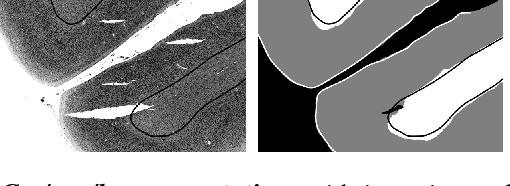

Microscopic analysis of histological sections is considered the "gold standard" to verify structural parcellations in the human brain. Its high resolution allows the study of laminar and columnar patterns of cell distributions, which build an important basis for the simulation of cortical areas and networks. However, such cytoarchitectonic mapping is a semiautomatic, time consuming process that does not scale with high throughput imaging. We present an automatic approach for parcellating histological sections at 2um resolution. It is based on a convolutional neural network that combines topological information from probabilistic atlases with the texture features learned from high-resolution cell-body stained images. The model is applied to visual areas and trained on a sparse set of partial annotations. We show how predictions are transferable to new brains and spatially consistent across sections.